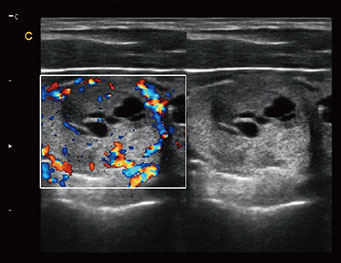

Kidney, C Mode